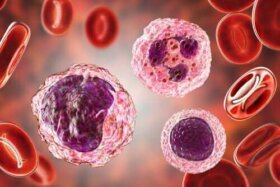

혈액 내 높은 단핵구 수치 및 치료에 대해 알아보자. 혈액에는 대부분의 사람이 일반적으로 알고 있는 것보다 더 많은 세포 유형과…